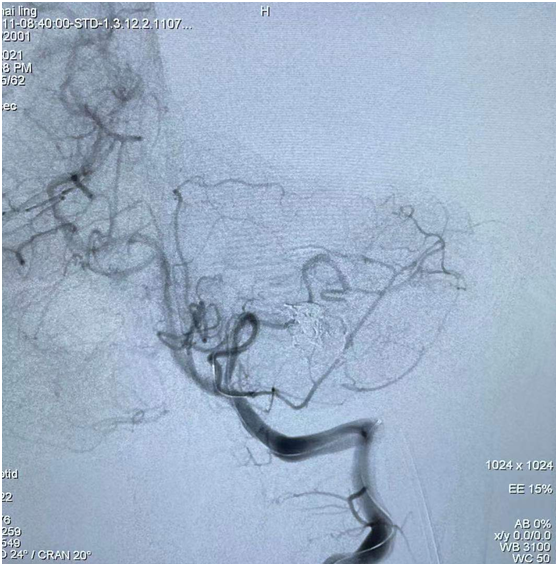

圖5:靜脈途徑注入栓塞劑,畸形團栓塞良好

圖6 :術(shù)后造影示畸形團完全不顯影,供血動脈及引流靜脈完好